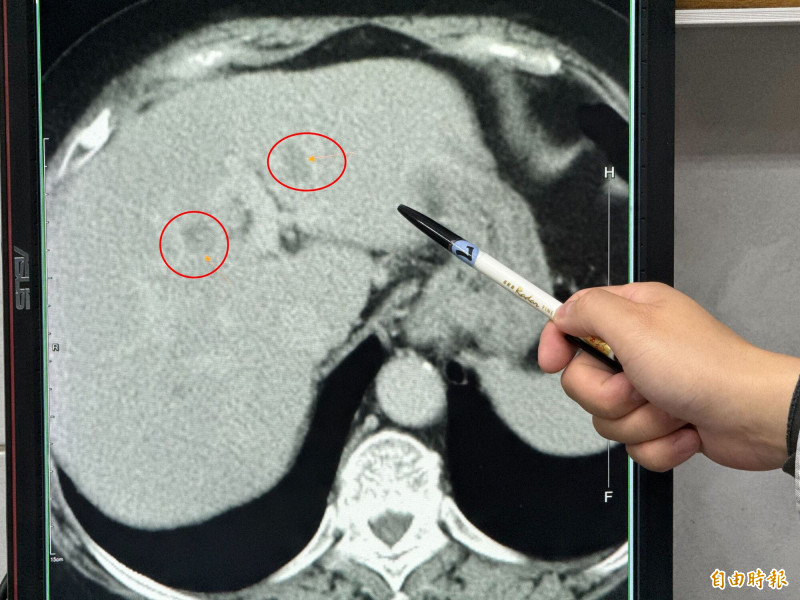

駐診在李綜合醫院的台中榮總一般外科醫師吳坤達表示,婦人在門診腸胃科做超音波時發現有重度脂肪肝及疑似腫瘤,進一步檢查確認在肝臟的左外側葉及左葉中部各有一顆腫瘤,擔心把患者左邊肝臟全切除後,患者肝臟功能恐無法運作,因此,使用「類機械手臂」多關節器械系統切除左外側肝葉,及術中射頻消融治療術消除腫瘤。

吳坤達說,即使是肝完全健康的年輕患者,肝臟切除手術至少要保留3分之1才能維持基本生理功能,該患者四到六成脂肪肝又有多顆腫瘤,為了讓她的肝臟能正常運作,脂肪肝切下了223克,大約一顆小蘋果的重量,沒有切除的腫瘤則採用射頻消融治療術讓組織壞死,手術進行大約3個多小時,失血量僅有約400C.C.,患者術後恢復良好。